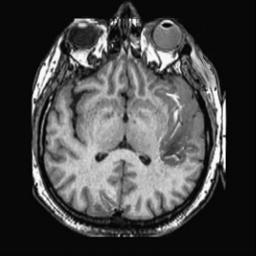

To demonstrate the effectiveness and efficiency of the proposed image fusion method , we conduct a set of comparative experiments on three image datasets. The first is composed by 8 pairs of multi-modal medical images and the second one contains 15 pairs of multi-focus gray or color natural images. These two datasets are often used in many related papers and some examples are shown in Figure 3(a) and Figure 3(b). The third one is a new multi-focus cervical cell image dataset collected by ourselves, which consists of 15 groups of color images and each group contains a series of multi-focus cervix cell images with size of or , etc. Some source examples are shown in Figure 3(c). Our source code implemented in C++ along with the new multi-focus cervical cell image dataset is available online.

We first evaluate the performance of the proposed method under varying total number of octaves and number of layers sampled per octave. The fused images of a pair of multi-modal medical images with different and are shown in Figure 4. In this example, on the one hand, when only 1 or 2 octaves are involved in constructing the DoG pyramid, the fused images fail to keep the integrity information of large size objects (e.g. eyeballs), while by increasing the value of , the integrity information of eyeballs is preserved. On the other hand, although not as significant as the increase of octave numbers , the fused image can contain more details by the increase of layer numbers . The corresponding objective quality metrics are shown in Figure 5. As shown in Figure 5(a), most of the metric values are improved as the number of octaves increases with the fixed layer numbers 3 in the global tendency and each of them tends to be stable when the number of octaves is 5. To get a relatively good quality from Figure 5(b), we can notice that some of the metric values can get a good performance when the number of layers is 3, such as the MI, SSIM, QI and VIF, though there are only a little change of all the metric values by increasing the number of layers with the fixed octave numbers 5. Because it will result in more computation burden with the increase of the value and , and for different kinds of source images, there are different performance with the diverse parameter settings. To get a trade-off between them in our experiments, we set for the multi-modal dataset, for the natural datasets and for the multi-focus cell dataset, respectively.

Figure 6 shows the fused images obtained by different methods with the multi-modal source images shown in Figure 3(a). As shown in these figures, the proposed method can produce images which preserve the complementary information of different source images well. Moreover, due to the scale-invariant structure saliency selection, our method can keep the integrity information of large size objects and the visual details simultaneously. Although the fused image generated by other methods can also capture the details to some extent, all of them fail to keep the integrity information of large size objects such as the eyeballs. Furthermore, from Figure 6(k)-6(t), the DTCWT, GFF, IM and NSCT methods may decrease the brightness and contrast while the proposed method can preserve these features and details without producing visible artifacts and brightness distortions.